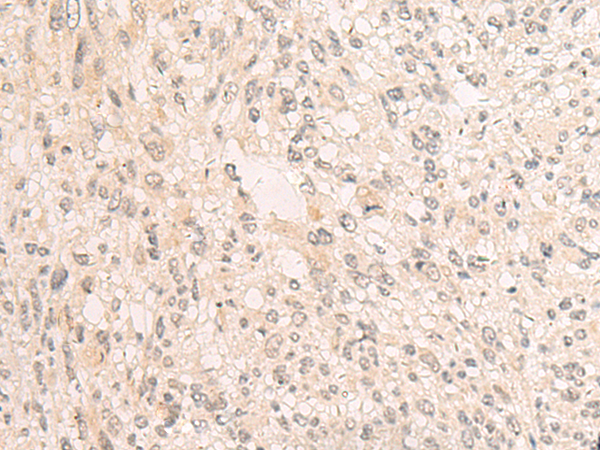

分类: 科研抗体货号: P13543别名: TFIIIC102; TFIIICgamma; TFiiiC2-102应用: IHC反应种属: Human